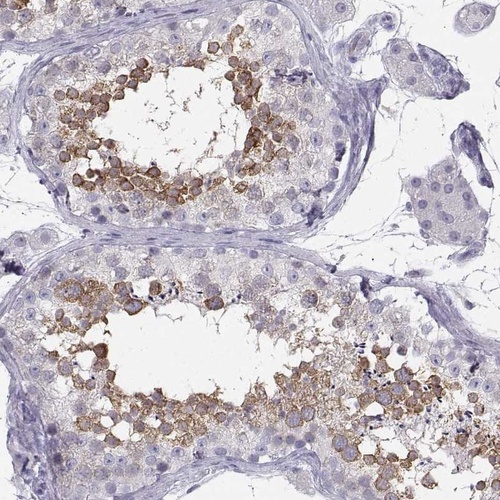

Immunohistochemistry analysis in human testis and endometrium tissues using Anti-SYCE1 antibody. Corresponding SYCE1 RNA-seq data are presented for the same tissues.